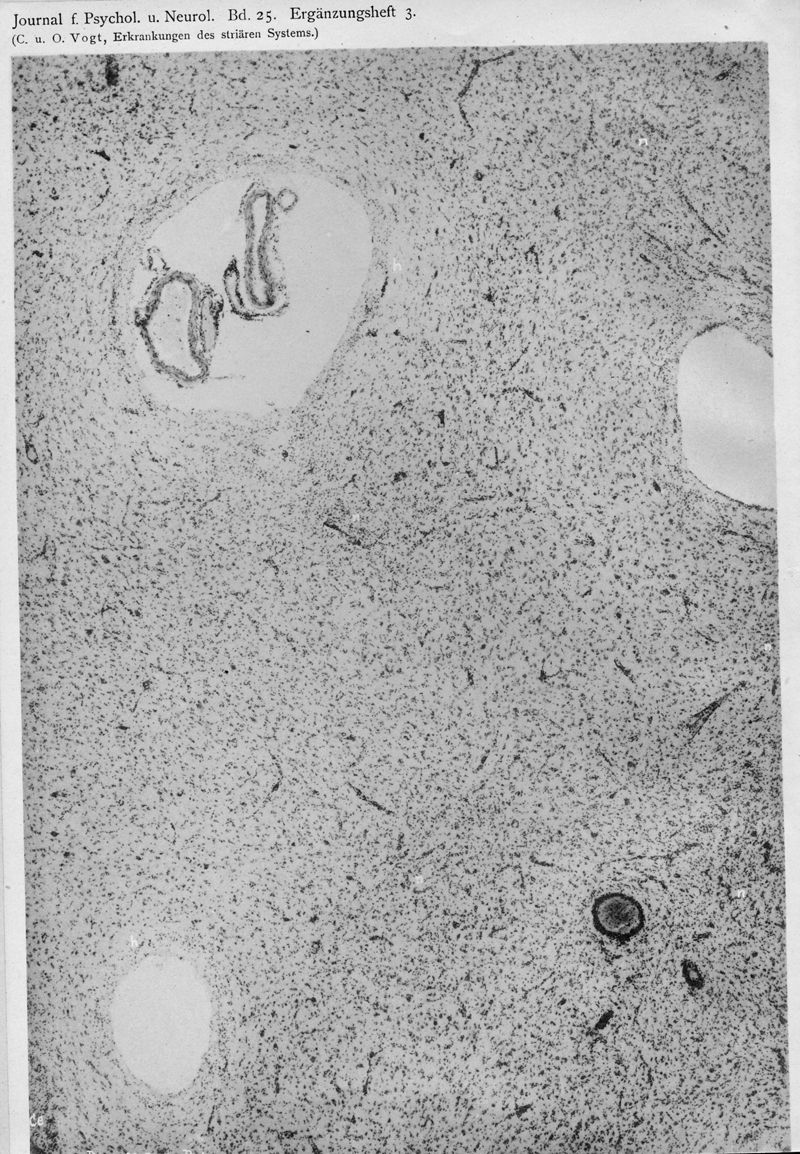

VOGT, Cécile / VOGT, O.

In : Journal für Psychologie und Neurologie,

1920, Vol. 25, pp. 627-846